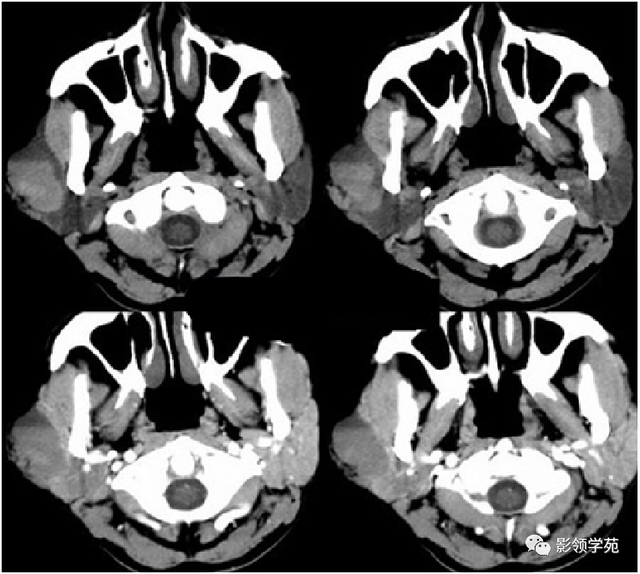

病例1:男性, 41岁,因“发现右耳垂下肿物1月余”:

病理:混淆瘤

病例2:女,30岁,发现右耳垂下肿物9月